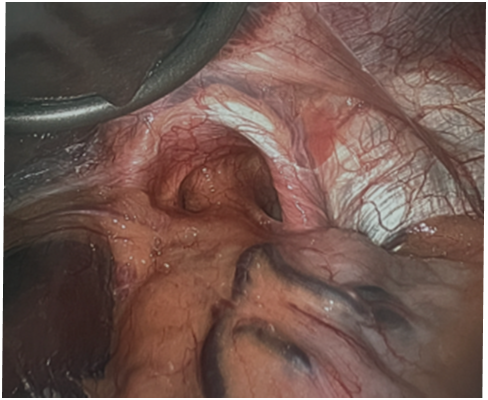

Laparoscopic hernia surgery is a surgical procedure in which a laparoscope is inserted into the abdomen through a small incision.

The laparoscope is a small fiber-optic viewing instrument attached with a tiny lens, light source, and video camera.

Laparoscopic surgery is performed in a hospital operating room under general anesthesia. The procedure involves the following:

- A camera attached to the laparoscope displays the image of the abdominal cavity on a screen.

- The surgeon makes three small incisions over the abdomen to insert the balloon dissector and trocars (keyholes).

- A deflated balloon along with the laparoscope is inserted and the balloon is inflated with a hand pump under direct vision.

- Once the trocars (key holes) are placed, the keyhole instruments are then inserted to repair the hernia.

- A sheet of mesh is inserted through the top keyhole and positioned and fixed in the abdominal wall to reinforce the repair and help prevent recurrent hernias. After completion of the repair the CO2 gas is evacuated and the trocars are removed and the tiny incisions are closed and dressed with a sterile bandage.